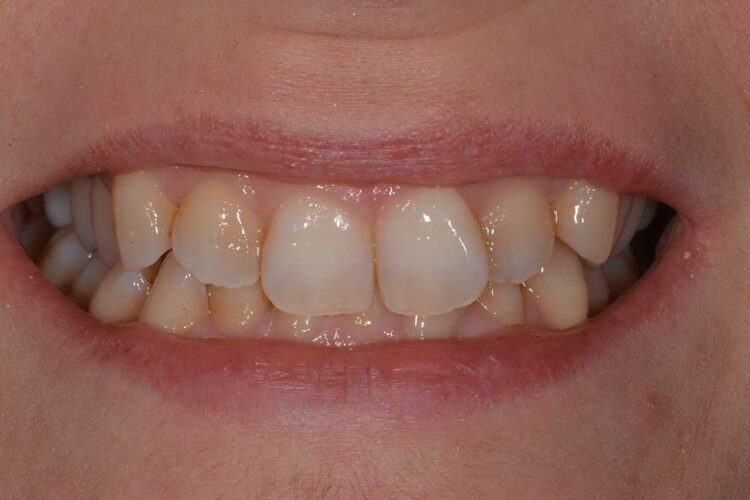

Ortodonzia allineatori – caso clinico 1